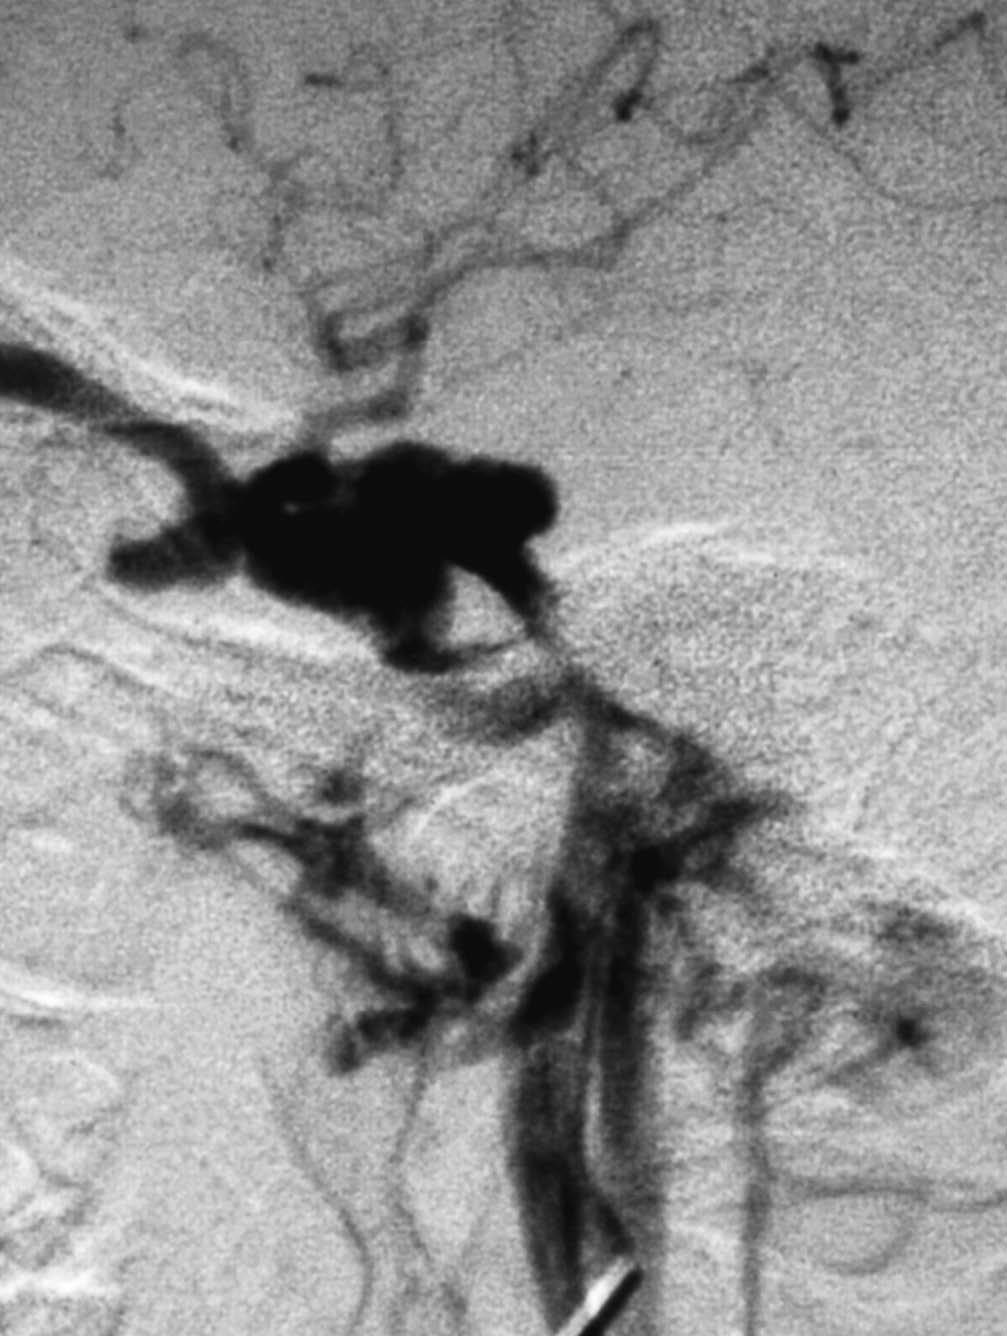

En los casos en los que el tratamiento conservador no ha sido eficaz10, cuando existen manifestaciones clínicas o angiográficas que asocian mal pronóstico, que ya hemos comentado, está indicada la terapia endovascular. La vía de abordaje puede ser arterial o venosa. Inicialmente se prefería la colocación de balones por vía arterial27-29. Con este procedimiento se conseguía cierre de la fístula con preservación de ACI casi en el 90% de los casos, sin embargo la tasa de complicaciones mayores era del 5%, consistiendo en isquemia cerebral transitoria e infartos tromboembólicos o isquémicos30. Los pseudoaneurismas post-tratamiento aparecían hasta en un 44% de los casos y se debían al hueco dejado por el desinflado del balón, pero su trascendencia clínica era escasa28,31. Hoy en día este procedimiento ha sido sustituido por otros gracias al desarrollo y empleo de nuevos materiales y/o vías de abordaje32. Se prefieren los coils en la práctica habitual (fig. 4).

Fig. 4.--A) Arteriografía cerebral con inyección de contraste desde la arteria carótida interna (ACI) en proyección lateral demuestra la existencia de una brecha o fístula directa, de alto flujo, en la porción intracavernosa en una paciente de 28 años con antecedente traumático. Asimismo se observa flujo venoso retrógrado a la vena oftálmica, que está muy dilatada. B) Cateterización selectiva de ACI y colocación de coils en el seno cavernoso por vía transarterial. C) Control arteriográfico tras la embolización transarterial con coils, con inyección de contraste en ACI, en fase arterial y proyección lateral, donde se aprecia empaquetamiento del seno cavernoso. Persiste todavía la dilatación de la vena oftálmica, que desapareció a los pocos días, con mejoría clínica completa.

En nuestro grupo de 10 pacientes con FCC directa tratada mediante embolización, en 5 procedimientos el abordaje fue por vía arterial exclusivamente, colocando como material embolígeno en 2 casos balones y en 3 coils (fig. 4). En 4 casos la mejoría de la sintomatología fue completa, mientras que en uno fue parcial. Tan sólo en un paciente se tuvo que realizar la exclusión completa de la arteria carótida ya que la ACI estaba muy deteriorada. Previamente realizamos el test de oclusión con objeto de conocer cuál sería el efecto de la exclusión carotídea.